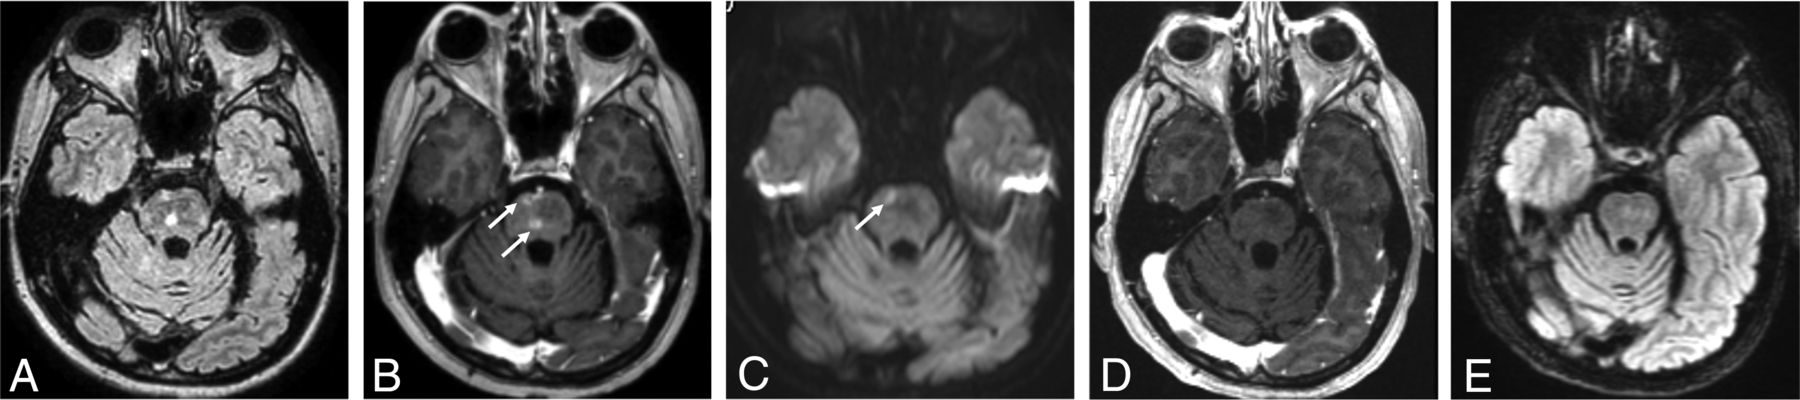

A 60-year-old man with brainstem SMART syndrome. He had a history of posterior fossa medulloblastoma treated with resection and 30 Gy of radiation therapy 16 years ago and presented with emotional lability and slurred speech. He completely recovered from the symptoms. A FLAIR image (A) shows hyperintensity in the central pons with peripheral patchy enhancement on the axial postcontrast T1-weighted image (arrows, B). C, DWI shows focal restricted diffusion in the corresponding area of the enhancing lesion (arrow). D and E, After 6 months, a postcontrast T1-weighted image shows resolution of enhancement with residual slight FLAIR hyperintensity.

SMART syndrome is a rare late-delayed brain irradiation complication, which occurs from 1 to 37 years after radiation therapy.47 In 1995, Shuper et al48 first reported 4 pediatric cases of complicated migraine-like episodes 1–3 years after brain irradiation without detailed MR imaging features, and in 2006, Black et al6 proposed diagnostic criteria of SMART syndrome, including clinical and imaging features. However, the signs and symptoms are known to occasionally be persistent, recurrent, or followed by infarction.4,8 Furthermore, migraines are one of the common clinical features but do not always occur, despite migraines being eponymous of this entity.5 Regarding imaging features, apart from classic cortical changes, the brainstem has been suggested to be involved (Fig 4),47,49 and T2WI and FLAIR hyperintensity in the cortical and subjacent white matter may occur and last for an extended period.5 DWI, SWI, and T2*WI, which are commonly included in brain MR imaging protocols, could show alterations in acute attack regions and provide a prognostic factor for clinical recovery.5 With reference to these clinical and imaging characteristics, the diagnostic criteria proposed in 2006 could be modified as suggested in Table 1, with the above-mentioned clinical and imaging updates. The main additions to the criteria proposed in 2006 are as follows: 1) The clinical signs and symptoms may be persistent, and 2) T2WI and FLAIR hyperintensity in the cortex and subjacent white matter in the irradiated areas may occur and persist.